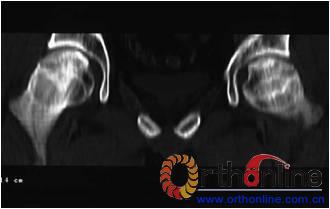

图1 女,22岁,(1)双侧股骨头坏死右侧B型,左侧C1型;(2)打压植骨术(加入BMP2)后5年,CT显示植骨生长良好,关节功能正常(Harris评分96分);(3)术后7年关节功能维持正常,股骨头维持正常外形